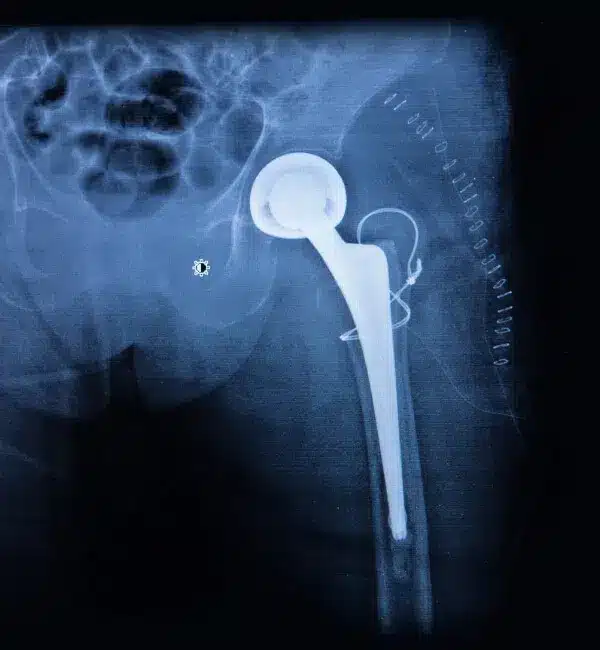

Endoprotezoplastyka biodra pozwala zlikwidować przewlekły ból, przywrócić ruchomość i umożliwia wieloletnie, stabilne funkcjonowanie stawu.

Nasze podejście opiera się na wyborze najbardziej efektywnych i jednocześnie możliwie mało inwazyjnych technik, zgodnych z najnowszymi zaleceniami ortopedycznymi. Endoprotezy dobieramy indywidualnie – korzystamy głównie z implantów bezcementowych o wysokiej trwałości, wykonanych z komponentów metalowych, polietylenowych lub ceramicznych.